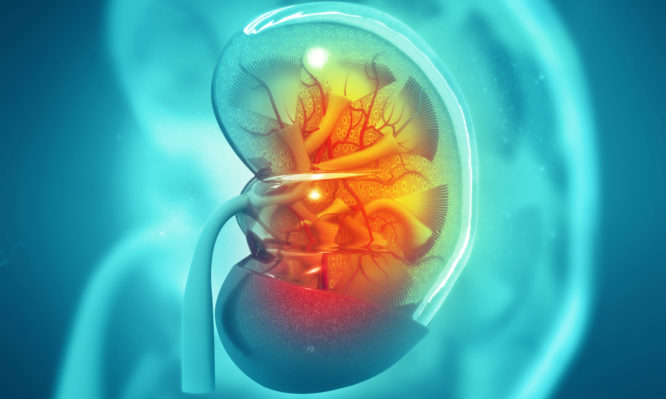

Με ποια συμπτώματα «χτυπάει» ο καρκίνος στους νεφρούς – Πολύ σημαντικό να εντοπιστούν έγκαιρα

Ο καρκίνος του νεφρού αρχίζει όταν τα υγιή κύτταρα σε ένα, ή και στα δύο νεφρά μεταβάλλονται και αναπτύσσονται...

Το αίμα στα ούρα και ο πόνος ή το αίσθημα βάρους στην μία πλευρά του σώματος, λίγο πάνω από...

Οι καρκίνοι του ουροποιητικού συστήματος είναι αρκετά συχνοί, καθώς προσβάλλουν χιλιάδες ανθρώπους σε όλο τον κόσμο, συμπεριλαμβανομένης της χώρας...

Πολλές πιθανότητες ιάσεως έχει ο καρκίνος του νεφρού όταν γίνεται αντιληπτός νωρίς, αλλά τα τελευταία χρόνια έχουν γίνει σημαντικά...